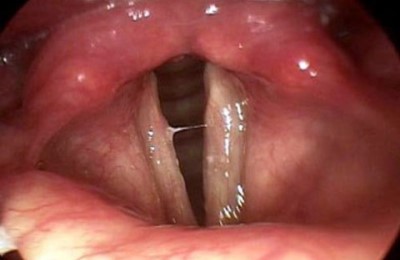

При осмотре выявляется резкое покраснение слизистой оболочки гортани. Также могут быть заметны дифтерийный налет или булезное утолщение слизистой при туберкулезе. При обычном, катаральном ларингите, вызванном вирусами, специфических изменений в слизистой оболочке нет.

Ларингит – это воспаление гортани, как правило, являющееся следствием вирусной инфекции. Это приводит к резкому изменению голоса, появляется слабость голоса и осиплость. Диагноз ставится на основании клинических проявлений. При проявлении симптомов более 3 недель необходимо выполнить ларингоскопию.